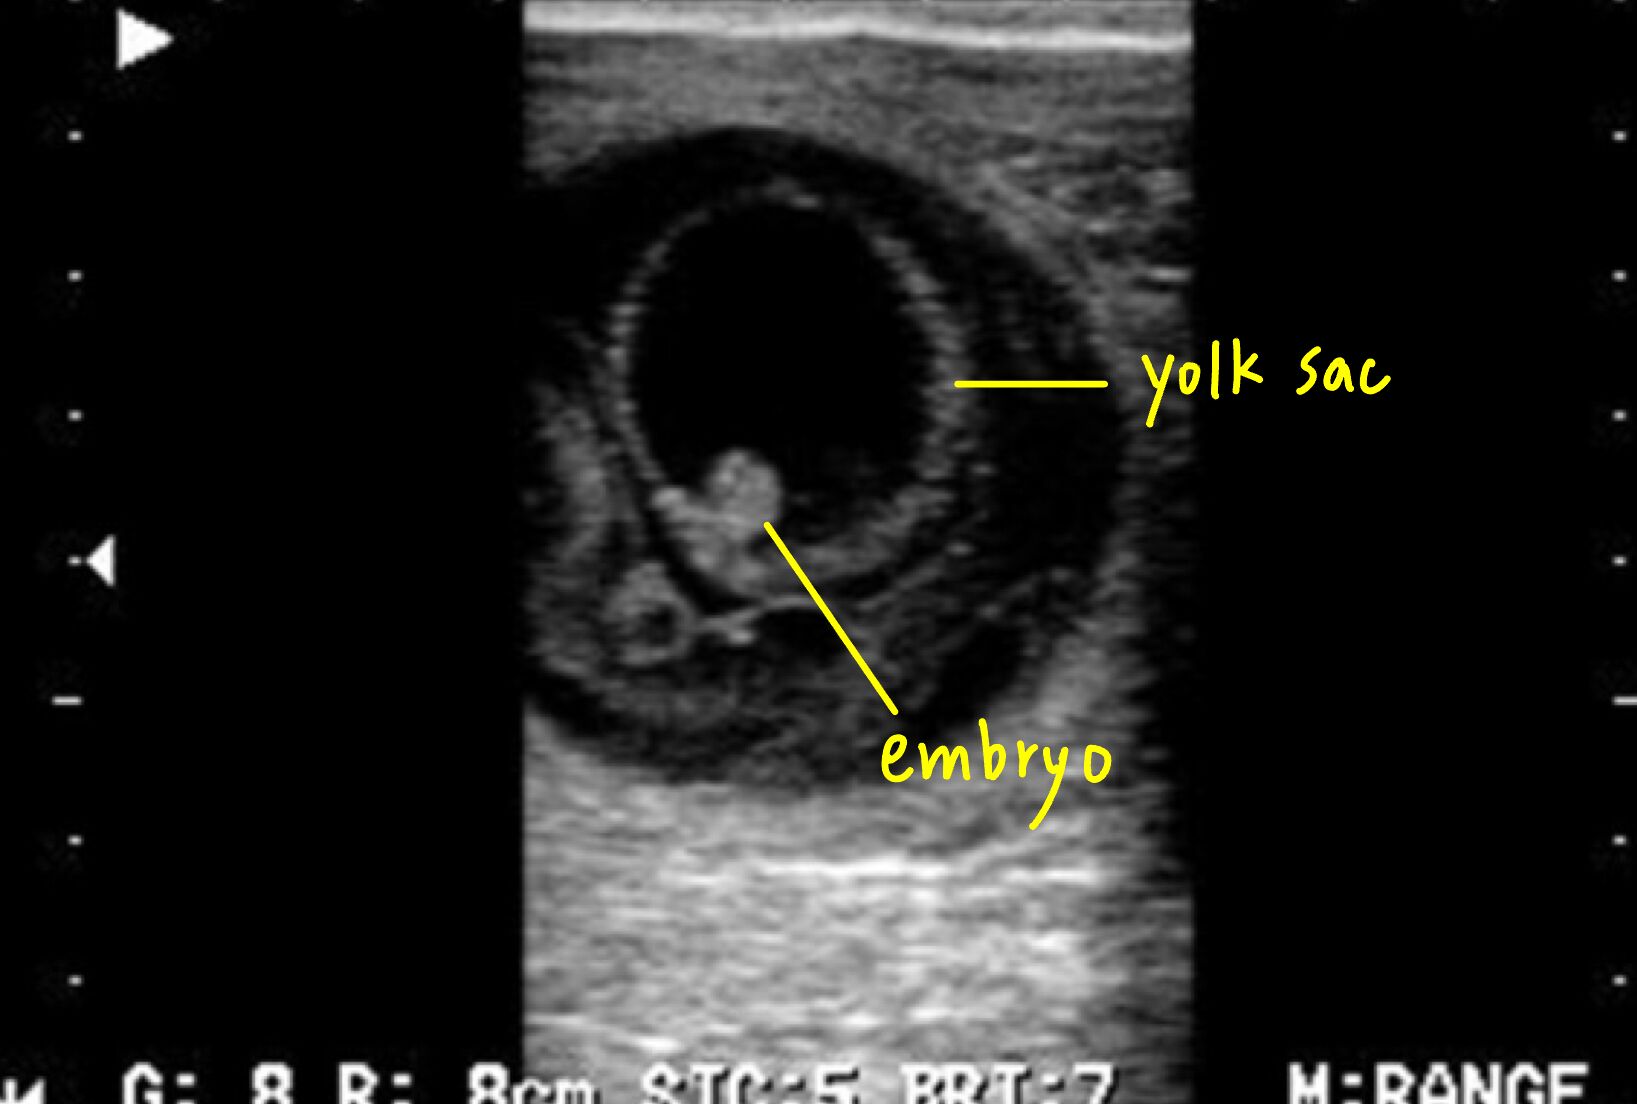

72.牧場牛隻配種後 60 天進行超音波妊娠檢查,於配種後未見發情,其子宮超音波影像如下圖,何者為該牛隻最可能之診斷?

這張圖片應該是45天的模樣

60 天時應該要有Bone formation了